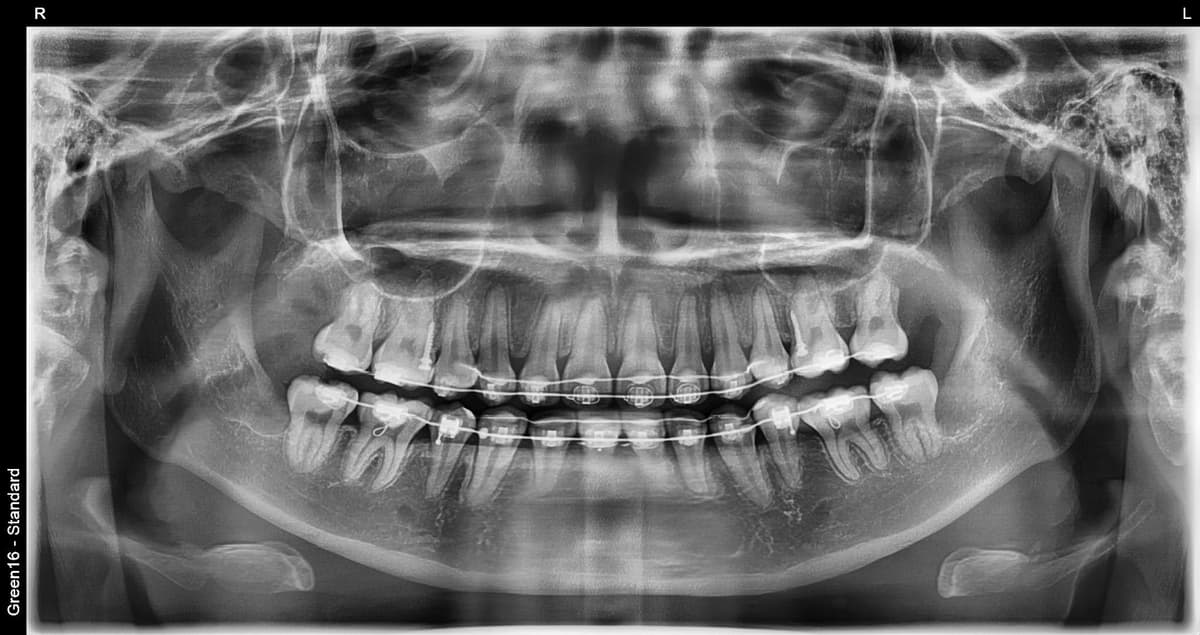

复杂的阻生智齿 - 即使深埋在牙龈中也没问题

贴近神经的智齿 - 无需担心神经损伤,安全拔除

水平阻生智齿 - 即使是横向生长的困难案例也可以处理

凭丰富的拔牙经验,

安全解决疑难案例

是的,可以。延世温雅牙科拥有丰富的拔牙经验和大学医院级别的系统来处理疑难病例。其他诊所转介到大医院的横向阻生和完全埋伏等困难病例,我们都能使用精确的3D CT诊断安全拔除。